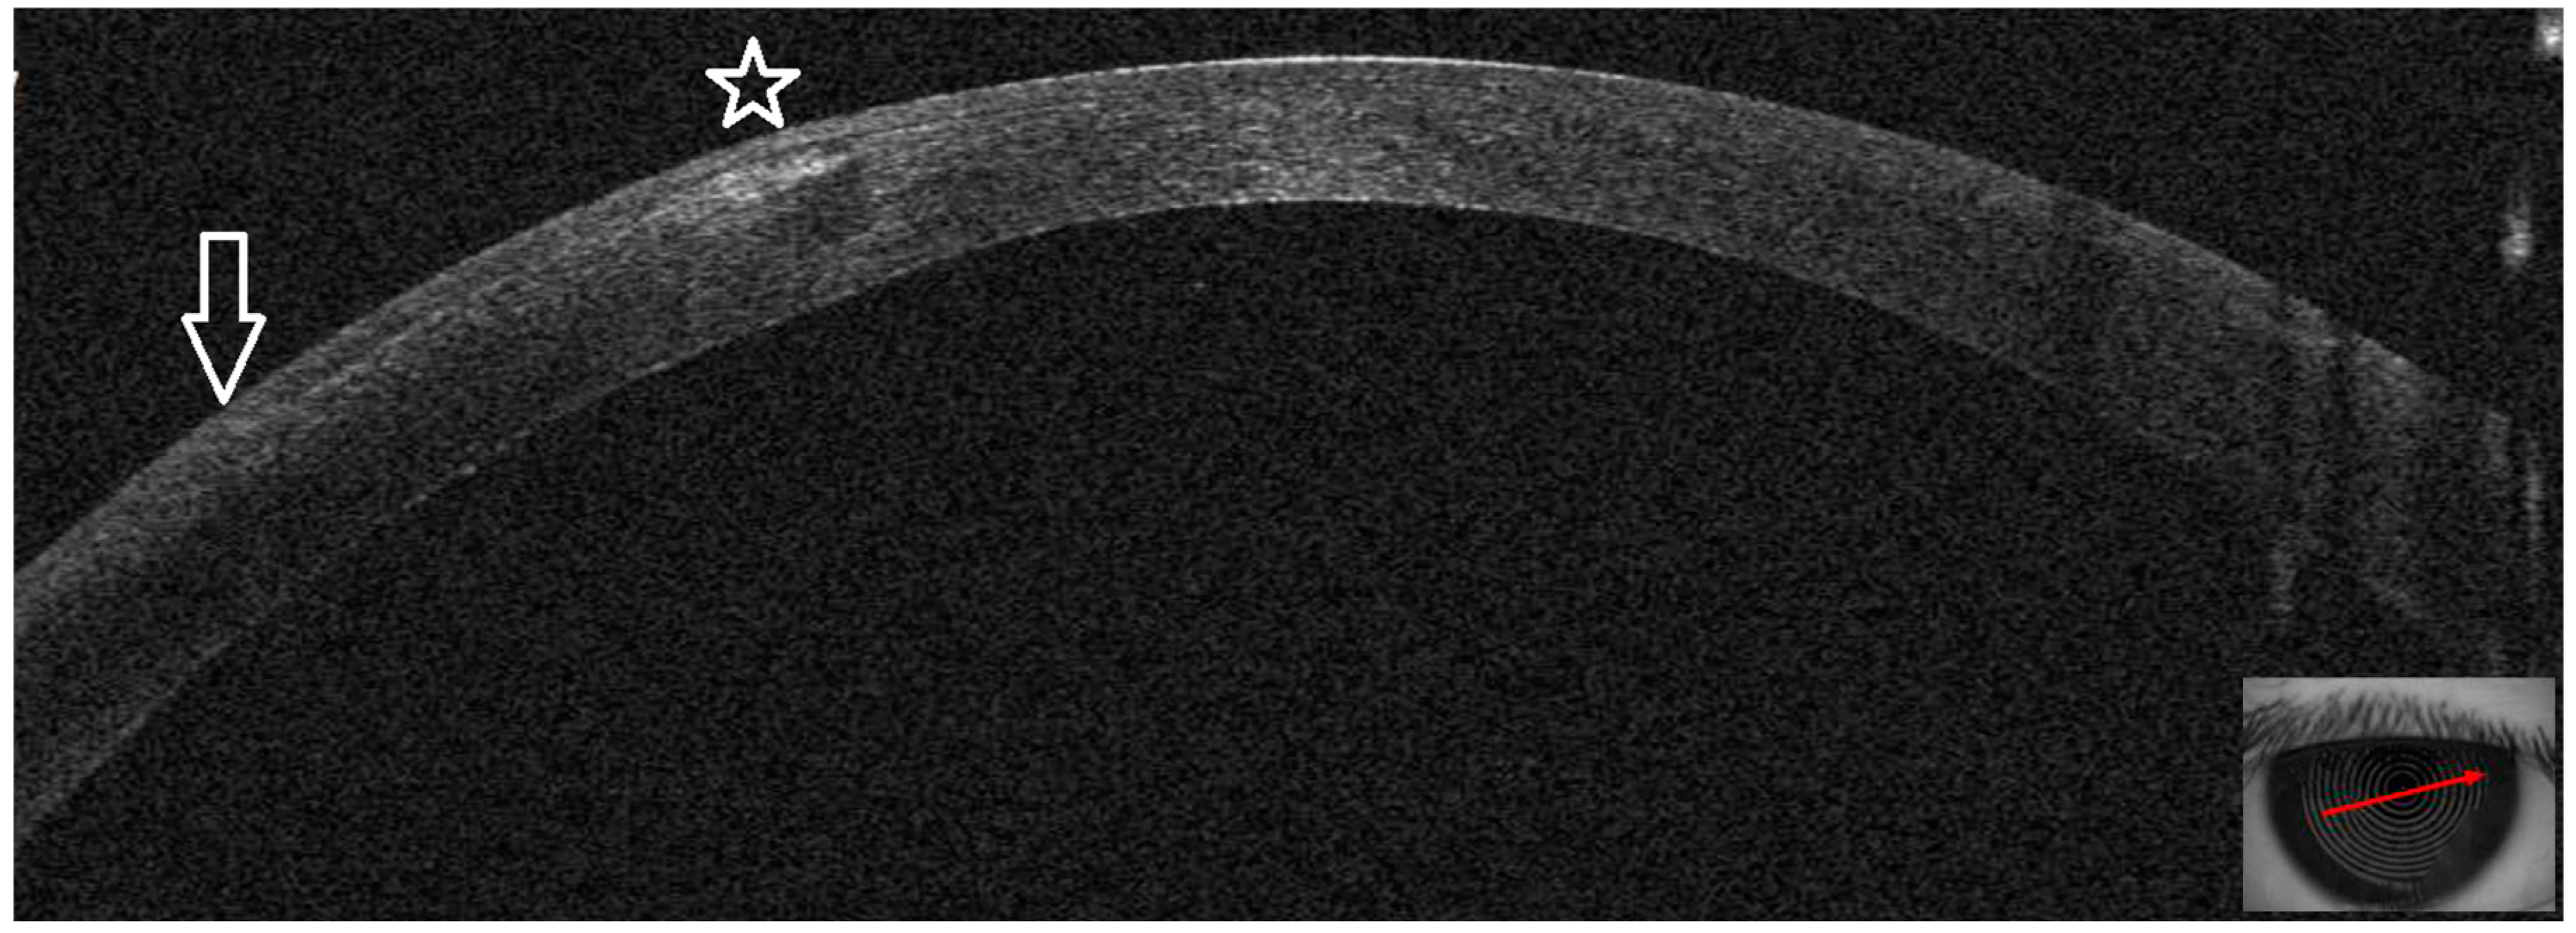

3.2. Patient #2